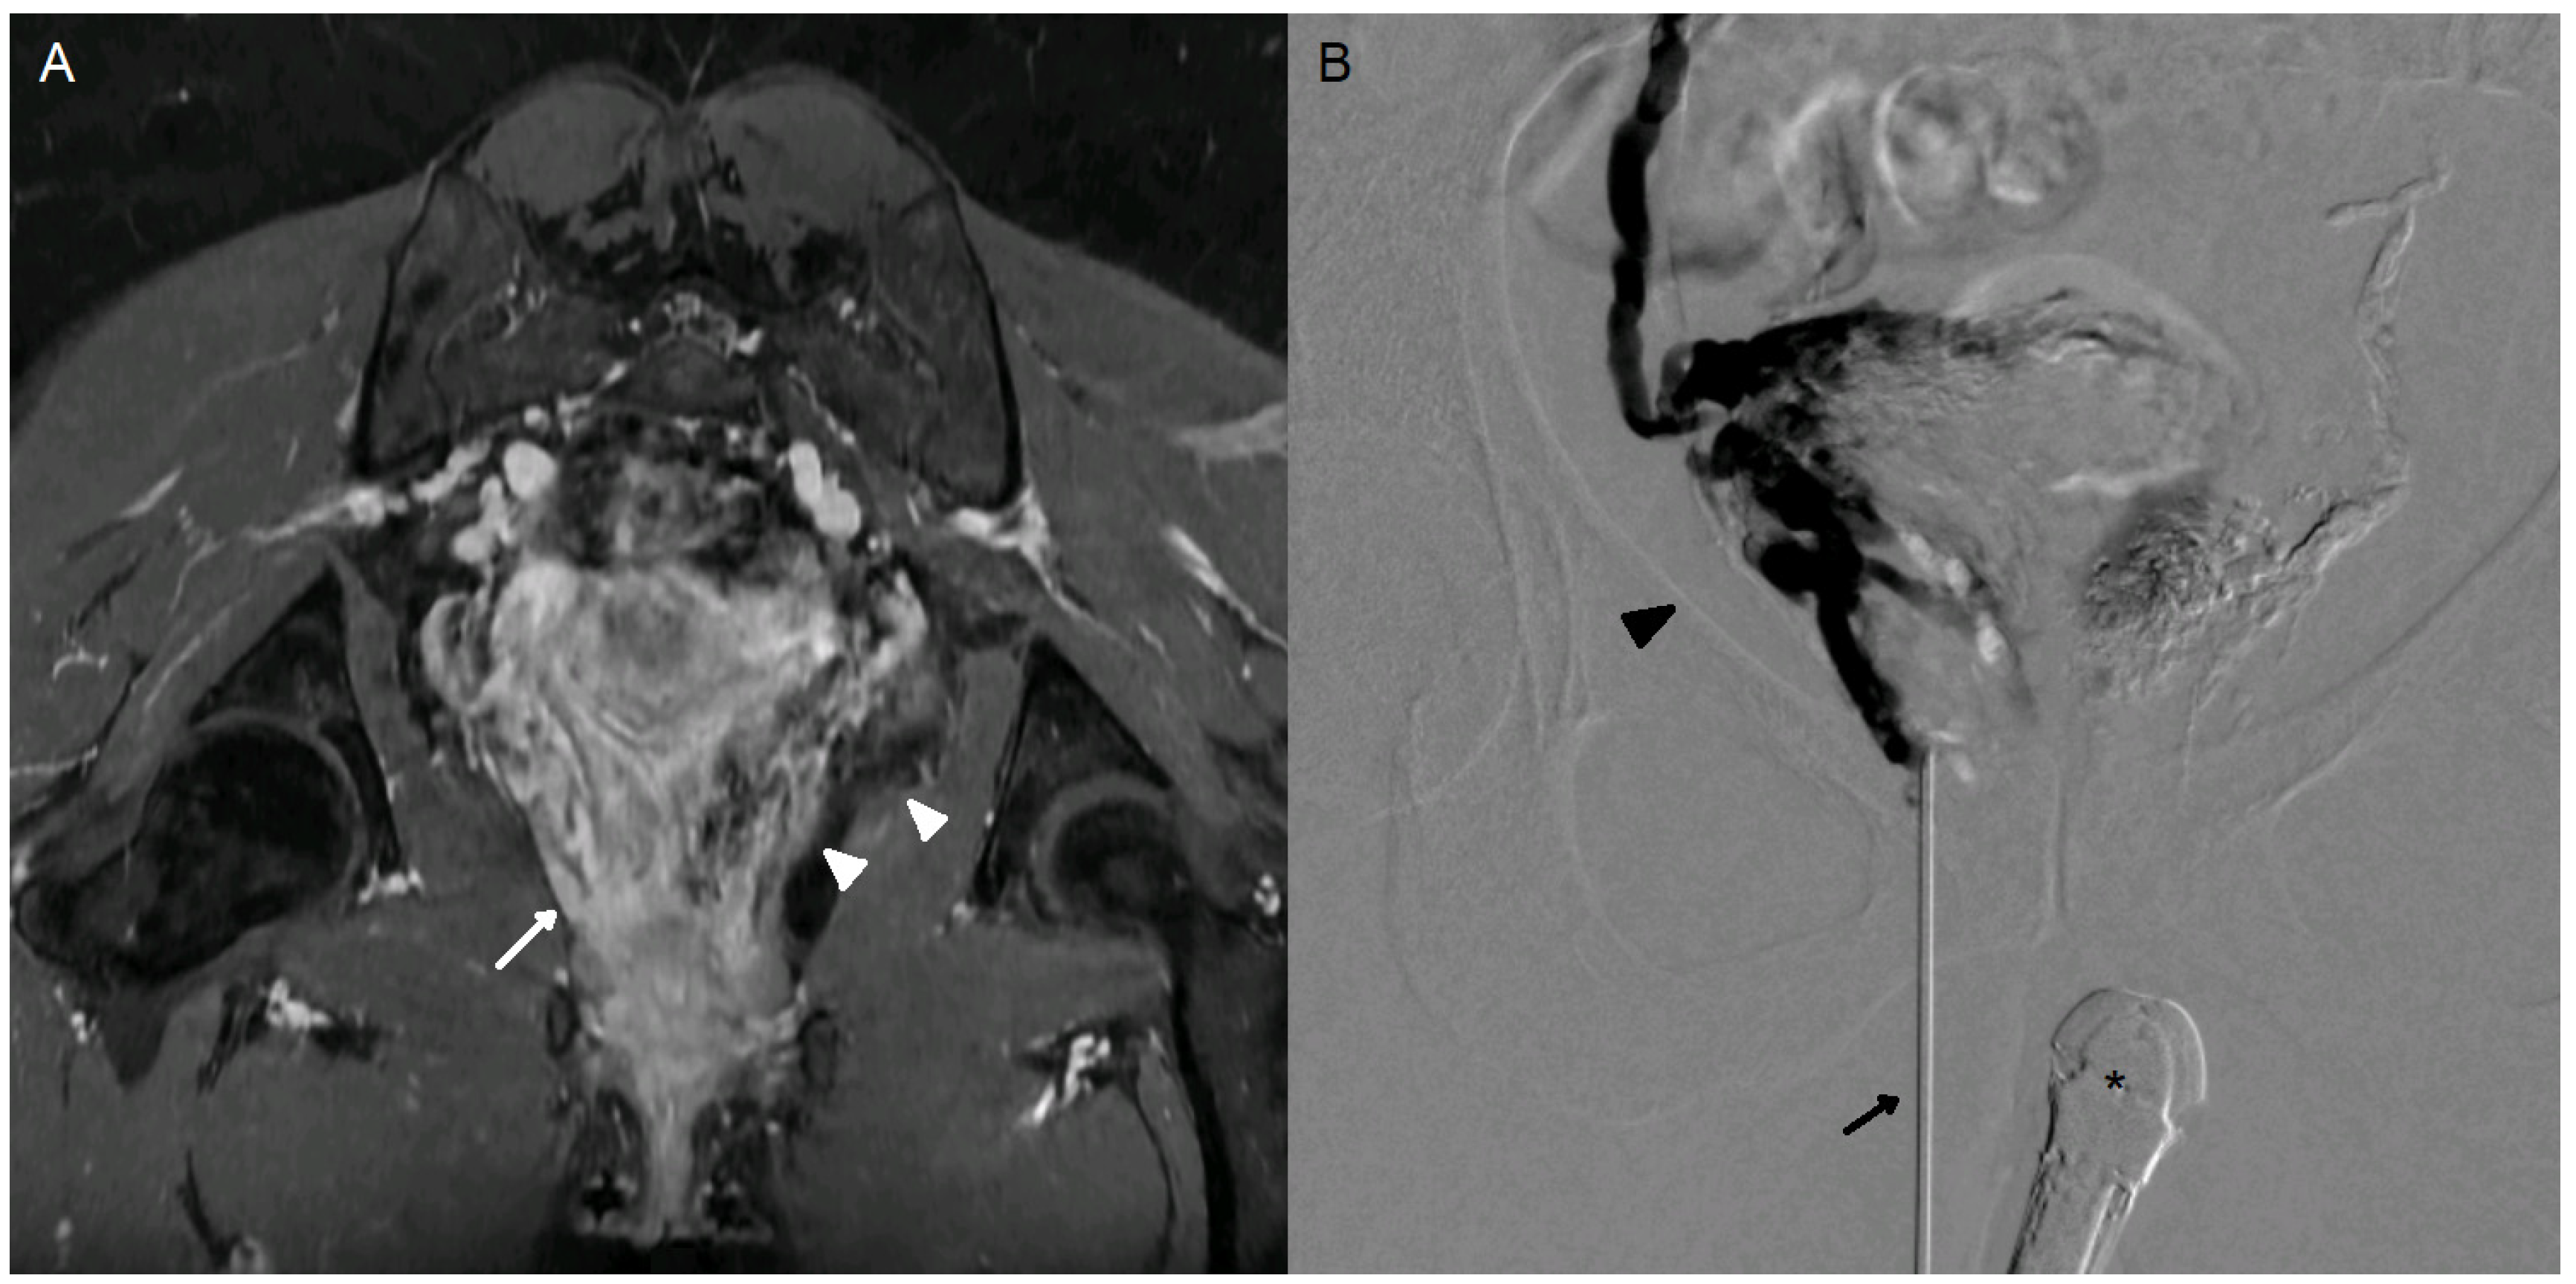

Figure 1. A 35-year-old woman (case n°6), G1P1, presenting with a 3-year history of chronic pelvic pain. Significant improvement in symptoms was achieved following endovascular embolization. However, dyspareunia (VAS 7/10) and postcoital pain (VAS 6/10) persist. (A) Oblique coronal MRI in the vaginal axis, LAVA FS sequence following gadolinium-based contrast injection (GE Systems, Signa Hero), demonstrating persistent right perivaginal varices (white arrow). The embolic agent (Onyx) is clearly visualized on this 3D gradient-echo sequence as a susceptibility artifact in the left perivaginal varices (white arrowhead). (B) Percutaneous puncture of right perivaginal varices (dark arrowhead) with a n18-gauge needle (dark arrow) under endovaginal guidance (*). Slow injection of iodinated contrast agent demonstrating opacification of the entire perivaginal and peri-uterine variceal network on the right side.